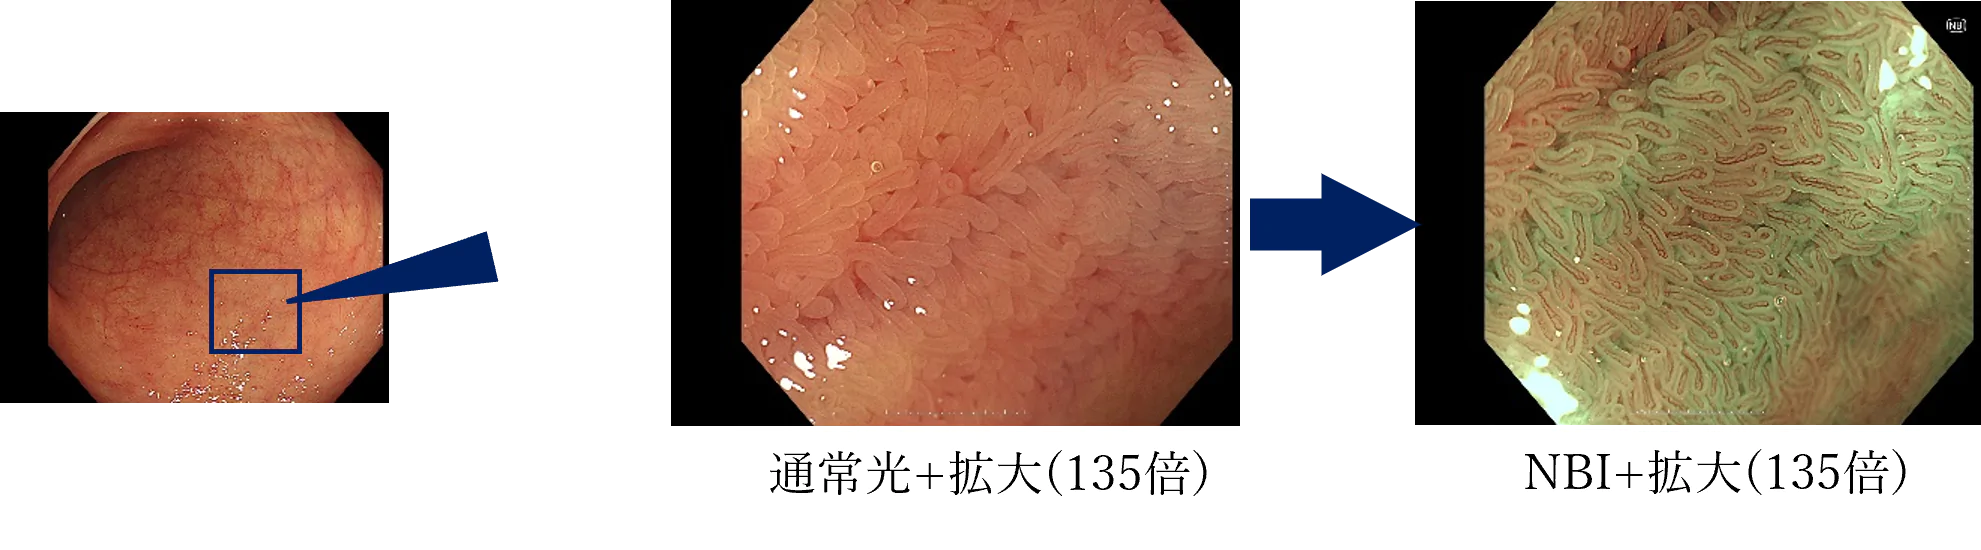

NBI(狭帯域光観察)

がんの増殖には血管からの栄養補給を必要とするため、病変の近くの粘膜には、小さな血管が集まりやすくなります。そのため、この小さな血管の集まりをいち早く発見することが、がんなどの病変の早期発見には重要です。

そのために用いられる技術が、「NBI(Narrow Band Imaging)」です。NBIは、血液中のヘモグロビンに吸収されやすい紫と緑の2つの特殊な光を照らすことで、粘膜表層の毛細血管やそのパターンなどが強調して鮮明に表示される観察技術です。これにより、通常光による観察では見えづらかったがんなどの病変の早期発見に貢献することが期待されます。

また、最適な治療判断には病変診断も重要となります。NBIは血管や粘膜の詳しい観察をサポートし、その診断にも貢献することが期待されます。

高倍率光学ズーム搭載の拡大内視鏡

当院で採用している4K対応、高解像度の内視鏡用モニター、オリンパス®「OEV321UH」+大腸ビデオスコープ「CF-XZ1200I」により、最大拡大倍率135倍の高倍率・高画質拡大観察が実現可能です。また、高感度CMOSイメージセンサーの採用により、ノイズが少なくハイビジョンを上回る高画質(HQ画質)で観察することができます。